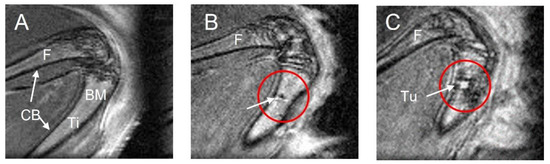

3.1. MRI Performance for Tumor Location and Phenotype Definition